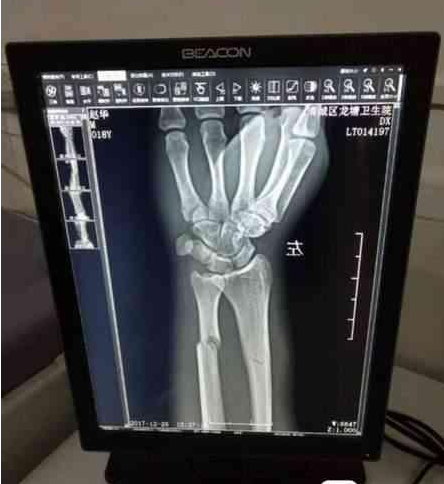

被砸断的骨头

原来10月21日下午3时,席军的父亲搭载2人(一人为本地口音,一人为外地口音)。途中摩托车摇晃几下,外地口音的乘客被摔倒在地,疼得嗷嗷直叫。席军的父亲马上打滴滴将伤者送到医院检查。在医院,伤者自称叫冉某。挂号、诊断、照片,发现冉某左手骨折。医生称:要住院3个月,医疗费至少两万元。听到这消息,席军的父亲脑壳都大了。

一会,又来了两个人,其中一人自称冉某的姐夫。嘘寒问暖后,“姐夫”开始做席父的工作:“冉某在阆中住院,家人照顾不方便,你还要多花钱,冉某在老家有医保,回家住院,可以少花些钱……不如你给笔钱作一次性了断。”席父觉得“姐夫”说得在理,就开始讨价还价。最后,席父以1.2万元了断此事。“冉某确实从我车上摔下地,从照的片上看确实是骨折,他回家治疗可以报销一些,冉某要1.2万元也算合理。”当时席父庆幸遇上通情达理的人,不然损失就更大了。